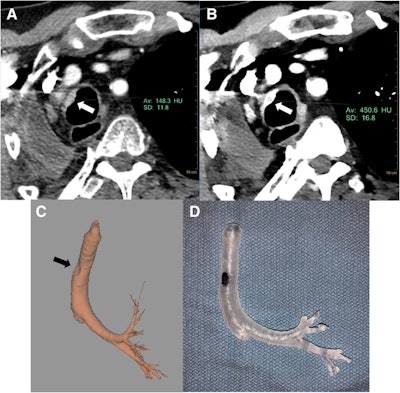

The researchers collected the conventional CT scans of four complex cases and subsequently obtained virtual monoenergetic images of the patients' DECT scans. Next, they performed image segmentation of the conventional CT scans and virtual monoenergetic images using software tools built into the CT scanner image viewer (IntelliSpace Portal 9.0, Philips Healthcare). After converting the images into 3D virtual models, they finally created a patient-specific 3D-printed model for each case using a desktop 3D printer (Form 2, Formlabs).

Overall, using DECT made the 3D printing segmentation process "faster" and "easier," as well as increased the operator's confidence during segmentation, the authors noted. These benefits allowed for the generation of more accurate 3D volume-rendered models and, in turn, more realistic 3D-printed models. In addition, the DECT data allowed the clinicians to create precise 3D-printed models in two cases for which using conventional CT yielded inaccurate 3D-printed models.